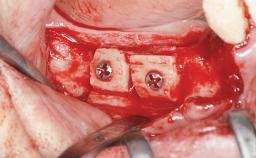

| Bone Augmentation | Horizontal|Simultaneous|Sinus Floor Elevation|Staged |

| Augmentation Materials | Xenogenous|Membrane |